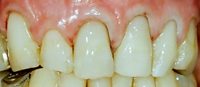

Die Abb. 1 bis 4 sollen als anschauliche Beispiele für gesunde und kranke Fundamente dienen.

Ein 31 Jahre alter Patient zeigt einen starke Zahnfleisch-Rückgang im Oberkiefer (Abb. 1 und 3) und wir beschliessen, diese Rezessionen zu behandeln.

Der Erfolg der Behandlung ist deutlich in den Abb. 2 und 4 zu sehen. Sehr augenfällig konnte die Situation um den Eckzahn im linken Oberkiefer verbessert werden (vergleiche dazu Abb. 3 vorher und Abb. 4 nachher).